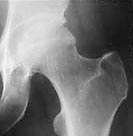

x-ray photo